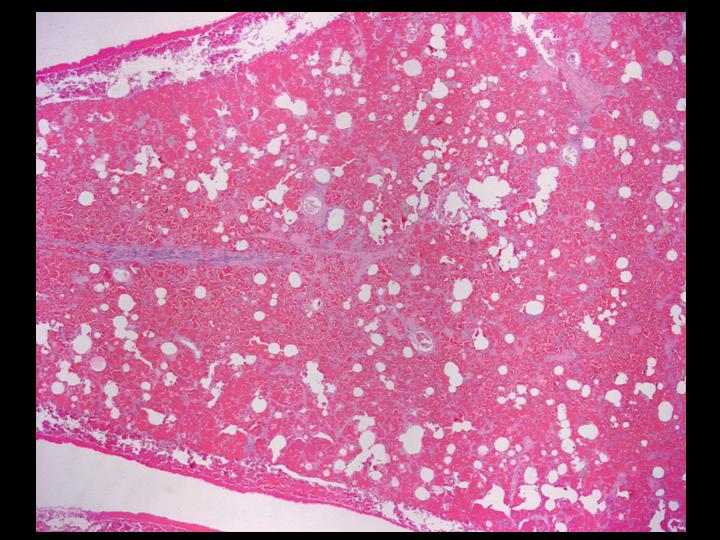

The lung biopsy was an adequate specimen comprised of a wedge of lung, 5.0 x 1.9 x 1.2 cm. The findings were jointly reviewed with the pathologists.

The next screen shows images from the lung biopsy:

| Figure 4-a | Figure 4-b | Figure 4-c |